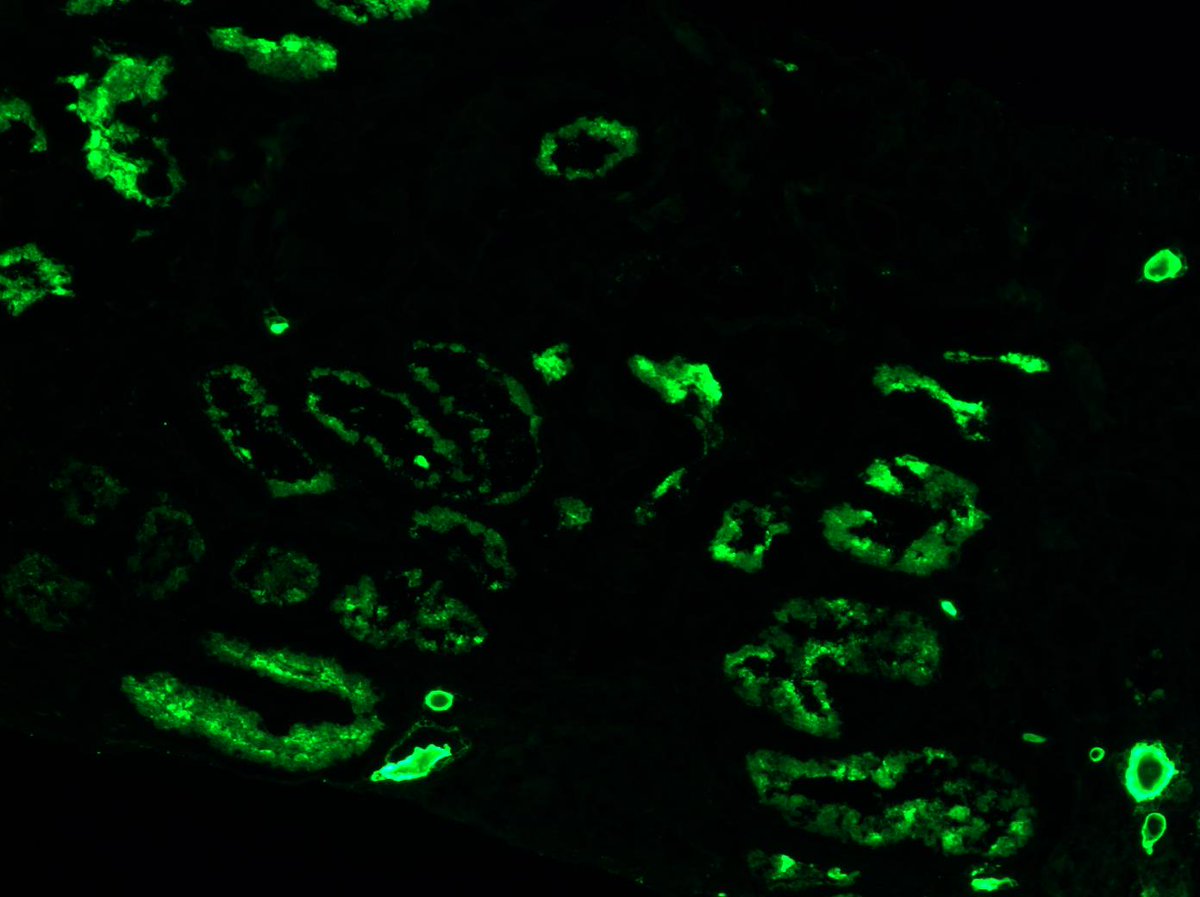

Long weekend often brings urgent cases. Here is one that was STATed, ended up showing anti-GBM GN. Diffuse crescents (nearly 100%). Linear IgG. #RenalPath